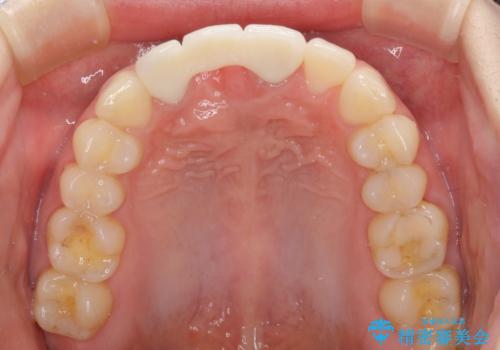

前院では、土台の金属を除去することは不可能であると言われたとのことでした。金属の土台が残っているとセラミックにグレーの金属色が透けて見えてしまうため、拡大鏡やマイクロスコープを用いて丁寧に除去し、天然歯の色に近いファイバーコアを植立することとしました。

金属色の透けた感じも歯肉からの出血もなくなり、自然な仕上がりの前歯となったので、患者様には大変満足していただきました。